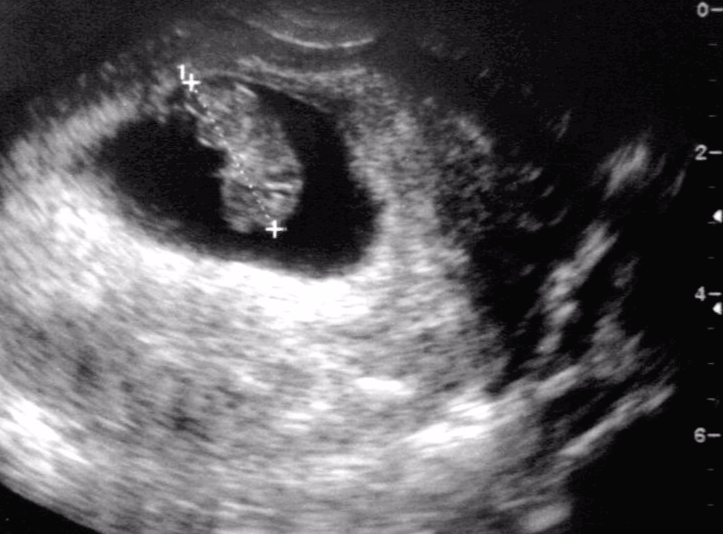

저희 아이의 경우는 정말 빼박으로

의사 선생님의 드립이나 힌트는 전혀 필요 없이

정밀초음파 검사 도중에 스쳐 지나가는 앵글만으로도

정말 화끈하게 자신의 성 정체성을 드러내 주었습니다.

16주 이후가 되면 성별 구분은

초음파 검사에서 더욱 확실하게 나타납니다.

보통은 아들에게만 있는 '그것'의 유무로

판단하는 것이 가장 일반적인 성별 판정 방법이죠.